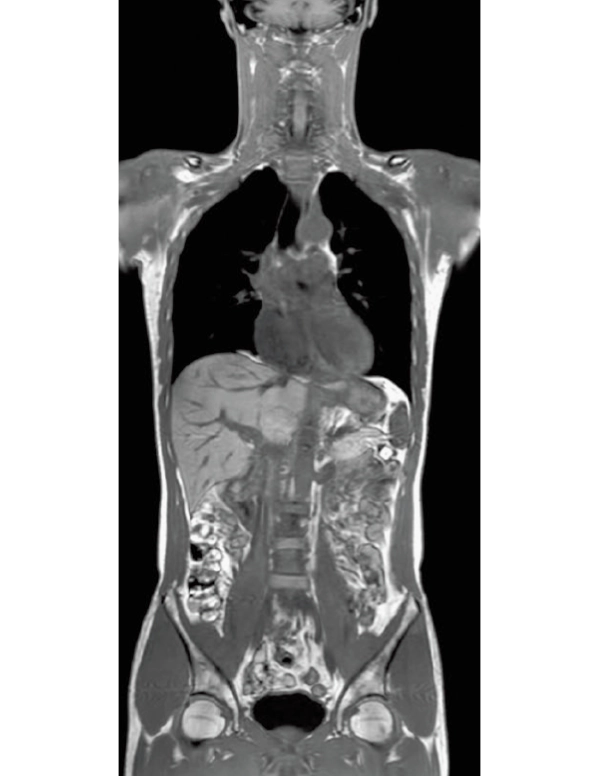

3D T1WI COR

2.2×1.5×1.5 mm

3st total scan time 0:54